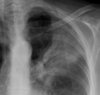

Raised hemidiaphragm (phrenic nerve injury) due to lung cancer

AC joint dislocation

Causes of white out on CXR

Pleural plaques: associated with asbestos exposure (but also previous empyema or radiotherapy); classically apex sparing

Retrocardiac mass: lung cancer until proven otherwise